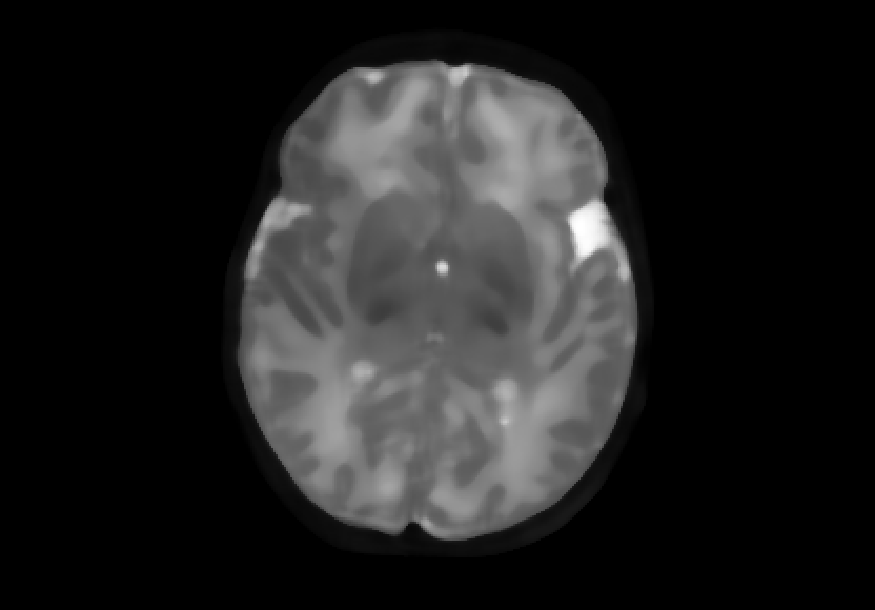

We also explored impulse noise corruptions, such as those introduced by noisy communications channels, faulty memory locations, or damage in channel decoders [6]. The impulse noise generating filter we used in this study is based on the salt-and-pepper (SNP) technique, which randomly generates black and white pixels on the image of interest. The function we used takes into account a parameter called prob, where 0 prob 0.5. A random number is generated for each pixel; if it is less than prob then the function paints the pixel with black, if it is greater than 1-prob then it paints the pixel with white, otherwise the pixel is left unchanged. In other words, the higher the value of prob, the noisier the output can become. We used different values for prob, in particular prob ={0.01, 0.03, 0.05, 0.07, 0.10, 0.15, 0.20}, to create seven different noisy datasets named snp_prob. Examples of axial slices are shown in Figure 4.